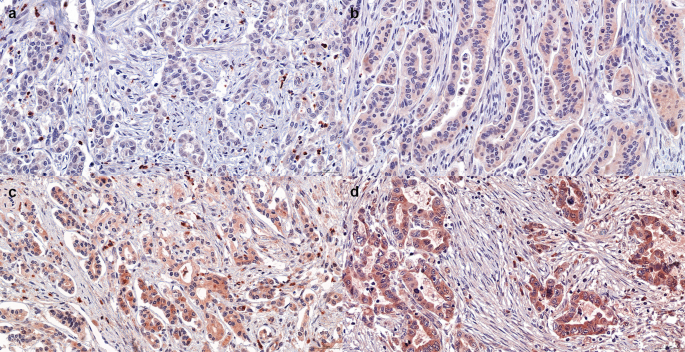

The NAT group had more patients with low MMP-8 immunopositivity than the up-front surgery group (p = 0.029) and only a few patients in both groups appeared negative for MMP-8 (Table 1). Different immunostaining patterns of NAT patients are demonstrated in Fig. 1. In the NAT group, low MMP-8 tissue expression associated with receiving preoperative radiation therapy (p = 0.043). Other clinical parameters such as age, sex, disease stage, histological grade, perineural invasion, perivascular invasion, NAT regimen and NAT response did not associate significantly with MMP-8 expression (Table 2).

Immunohistochemical staining patterns demonstrating Matrix metalloproteinase 8 (MMP-8) tissue expression in neoadjuvant therapy (NAT) patients. (A) Non-detectable MMP-8 expression in cytoplasm. (B) Low cytoplasmic immunopositivity. (C) Moderate cytoplasmic immunopositivity. (D) High cytoplasmic immunopositivity. Magnification 30x was used for all images.